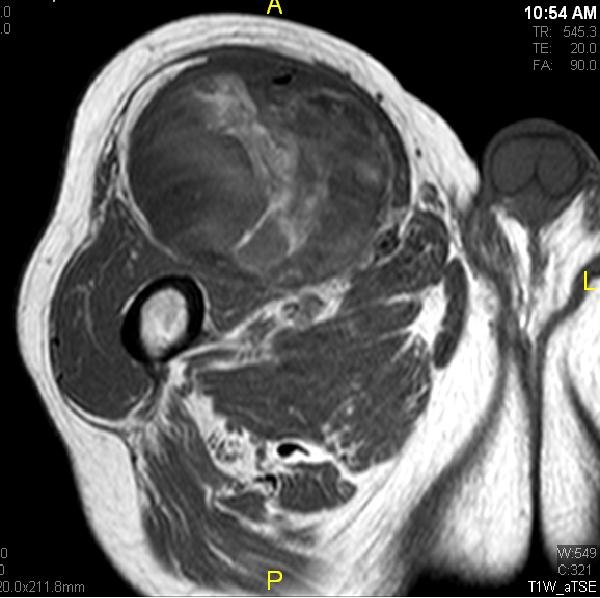

Fig. 7 & 8 Magnetic Resonance Image shows a large heterogeneous mass in the right thigh with low intensity signal on Axial (Fig. 7) and Coronal (Fig. 8) T1-weighted images admixed with high signal areas. The high signal areas represent low grade fatty tissue and low signal the dedifferentiated areas. Higher intensity signal is visible compatible with hemorrhage or necrotic tissue.

Fig. 9 Coronal fat suppressed T1-weigthed MR image demonstrates a large heterogeneous mass in the anterior compartment of the thigh with some areas suppressed corresponding with fatty areas within the tumor. Central hyper enhanced areas compatible with hemorrhage or necrosis.

Fig. 10 Axial T2 weighted MR image demonstrates a large well encapsulated heterogeneous mass with multiple thick internal trabeculations located in the anterior compartment of the thigh.